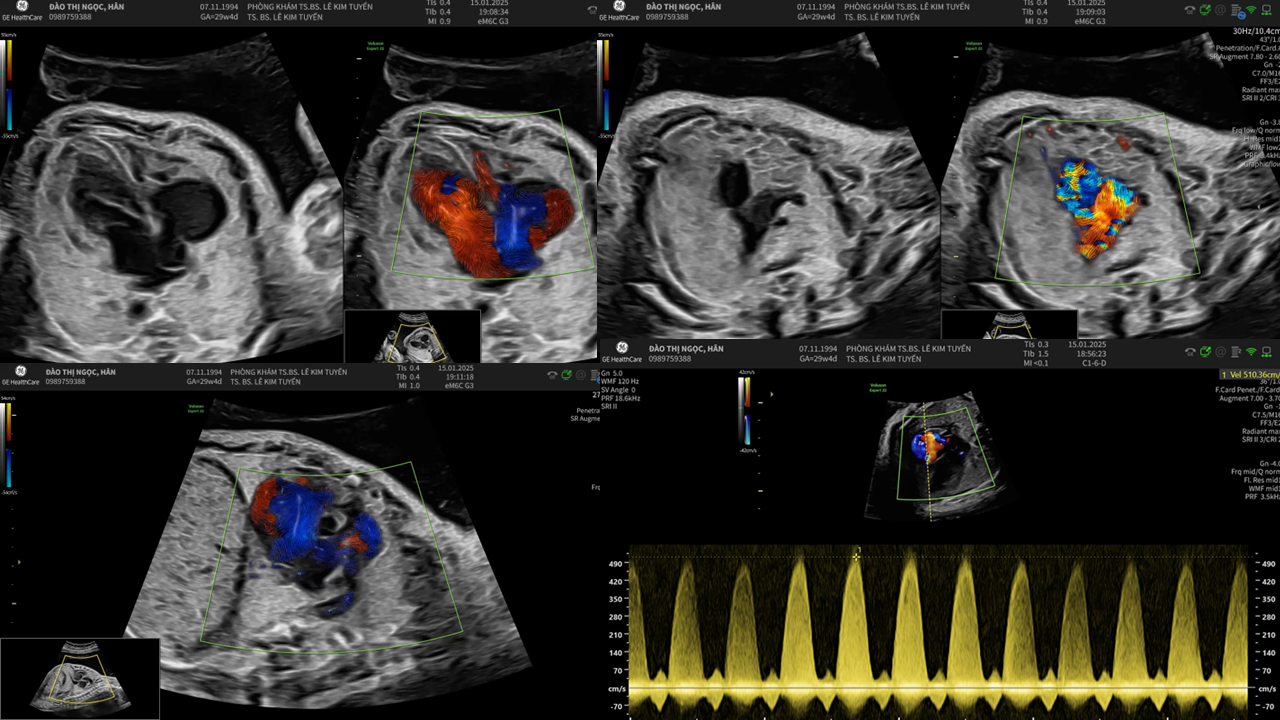

Áp dụng công nghệ Graphicflow trong phát hiện bệnh tim bẩm sinh cần cấp cứu sơ sinh

TS. BS. Lê Kim Tuyến